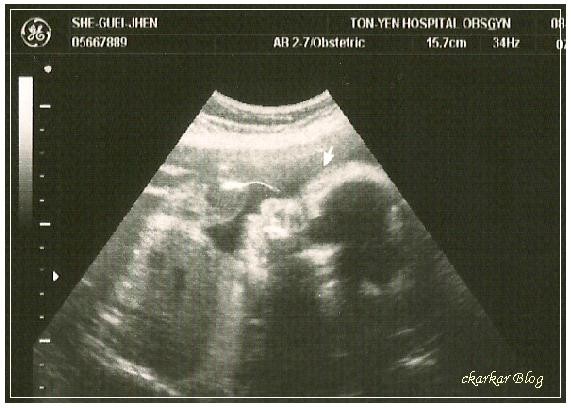

7/22沒想到產檢會喝的糖水,這麼快就輪到我喝了,確定老公下班的時間後一口氣把糖水喝掉,